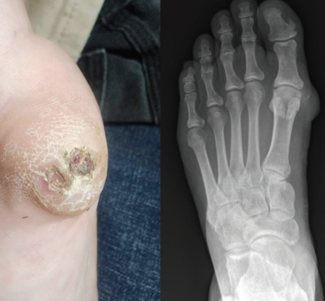

Os Cuboideum Secundarium

A rare accessory ossicle, the os cuboideum secundarium, is typically an incidental finding—but in high-risk feet, it can become clinically significant. This case highlights how an unrecognized plantar-lateral bony prominence contributed to...